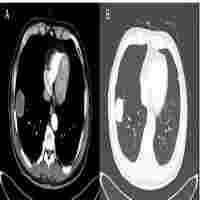

| Abstract | Pulmonary sarcomatoid carcinoma (PSC) is a rare subtype of non-small cell lung cancer with high malignancy and poor prognosis. Chemotherapy or radiotherapy do not usually provide satisfactory results in patients with PSC, especially in those with advanced-stage cancer. Targeted therapy and immunotherapy are more precise therapies that may be effective in the treatment of PSC; however, further research is needed. Here, we present a case of stage III PSC with obstructive atelectasis, which is more challenging and hinders treatment. Treatment with the PD-1 inhibitor camrelizumab and transbronchial cryoablation showed significant clinical efficacy. This type of combined treatment has not been reported previously for PSC. Thus, this case may provide a valuable reference for future clinical practice and research. |